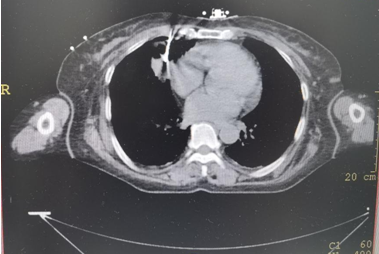

病例简介:一例小肠间质瘤伴右肺结节患者

拟行:IQQA-Guide导航下右肺穿刺活检术

▲上图:IQQA-Guide术中全程三维量化实时定位、跟踪、引导及监控,辅助医生精准穿刺

病理报告:低分化腺癌,该患者为双原发肿瘤。